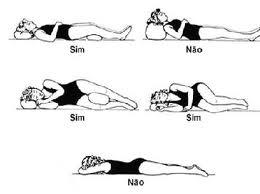

Whiplash ou chicote cervical

Whiplash ou popularmente conhecido como chicote cervical é um termo que se refere a uma lesão do pescoço causado quando ele de repente e/ou violentamente é sacudido em uma direção e, em seguida, em outra direção (movimento de hiperflexão/hiperextensão). Freqüentemente ocorrendo em acidentes automobilísticos o whiplash pode ocorrer na prática esportiva (boxe, esportes radicais, queda […]